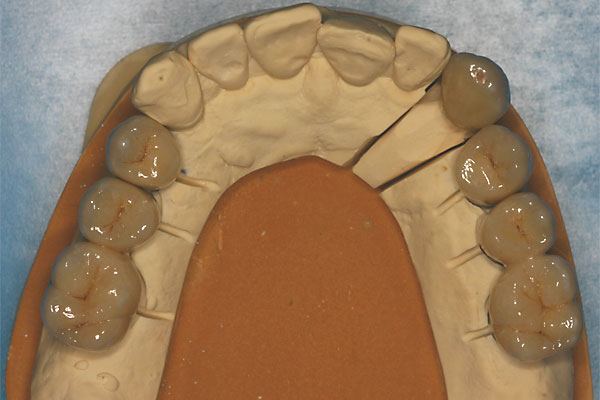

FOTO Meistermodell mit Laborimplantaten zur Herstellung der Brücken |

Metallkeramische, festsitzende Brücke |

FOTO vier kleine Brückensegmente ergeben die Oberkieferversorgung |